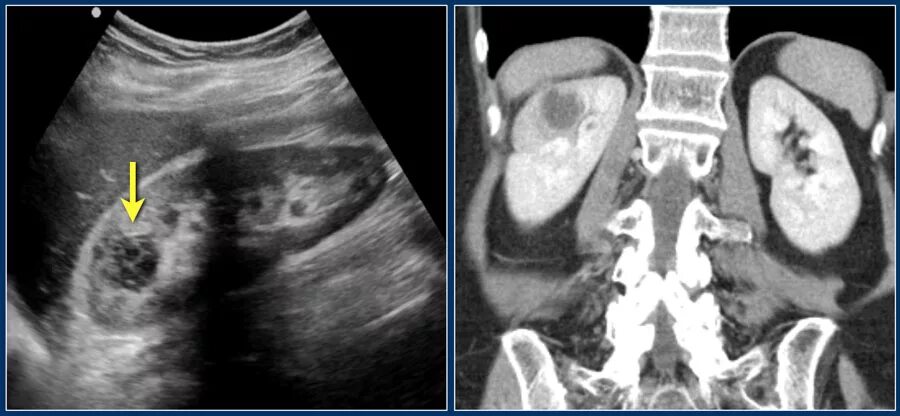

Солидное образование в малом тазу